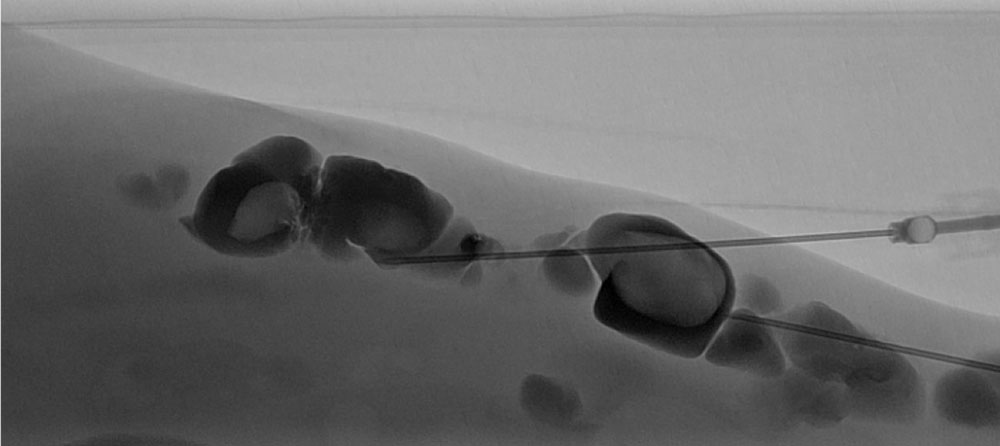

The normal organizing degradation of larger local thrombi or thrombophlebitis can lead to collagen deposition, which is palpable as a circumscribed induration over a longer period of time. If the thrombus then still cannot be completely degraded in the venous malformation, calcium deposition and increasing local, shell-like or popcorn-like calcification will occur over time. The final form is the calcified phlebolith as a round calcified lesion 1 cm in size on X-ray images of the venous malformation.